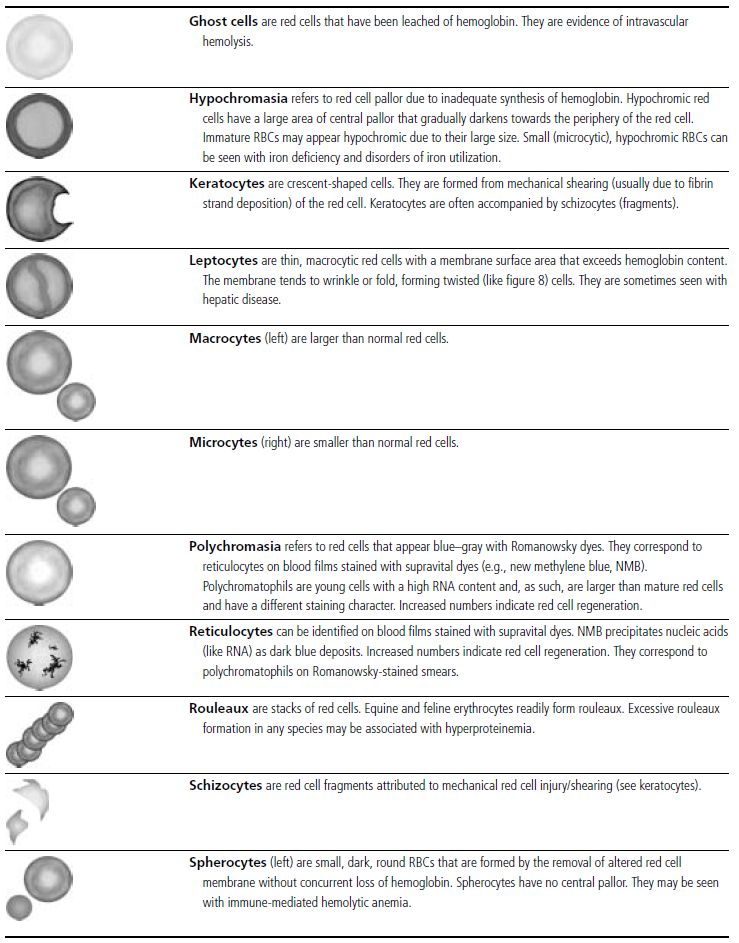

In the common domestic animals, mature erythrocytes are biconcave disks that are highly deformable, allowing them to travel through small capillaries and deliver oxygen to tissues (see Table 1.1). Erythrocyte aging and certain pathological conditions can cause RBCs to assume unusual shapes, which may result in increased rigidity. Rigid RBCs are susceptible to mechanical injury and are less effective in delivering oxygen. Exposure to stagnant environments (pooling of blood in a cavernous, hypoxic space), certain serum biochemical abnormalities, antibody-mediated membrane injury, and mechanical injury can alter the normal biconcave shape. Sometimes, RBC morphologic changes are associated with specific diseases or conditions, but the mechanism of the shape change is not clear (see Table 1.1 for diagrams of various types of RBC morphology).

See Figs 1.3–1.24 for pictures of various types of RBC morphology.

Table 1.1 Erythrocyte morphology